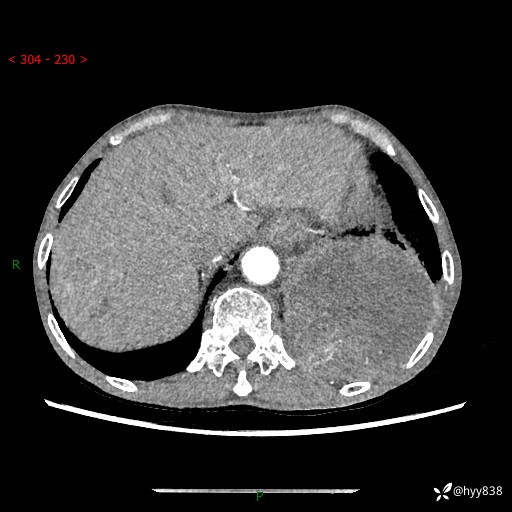

77岁/男,腹痛2月,CT发现左肺占位1天。巨大肿块,肺内或肺外来源…结果公布~

主诉:腹痛2月,CT发现左肺占位1天

现病史:患者于2025年9月间断左下腹胀痛,在当地镇卫生院行彩超检查考虑泌尿系结石,行止痛排石对症治疗未见明显好转;1天前腹痛症状加重,至当地市第三人民医院行CT检查:左肺下叶巨大团块状软组织影,考虑肿瘤性病变,建议增强CT检查;左侧胸腔积液;纵膈内淋巴结肿大;双肺肺气肿;右肺中叶纤维灶。为进一步求治,来我院就诊。

胸部CT平扫+增强